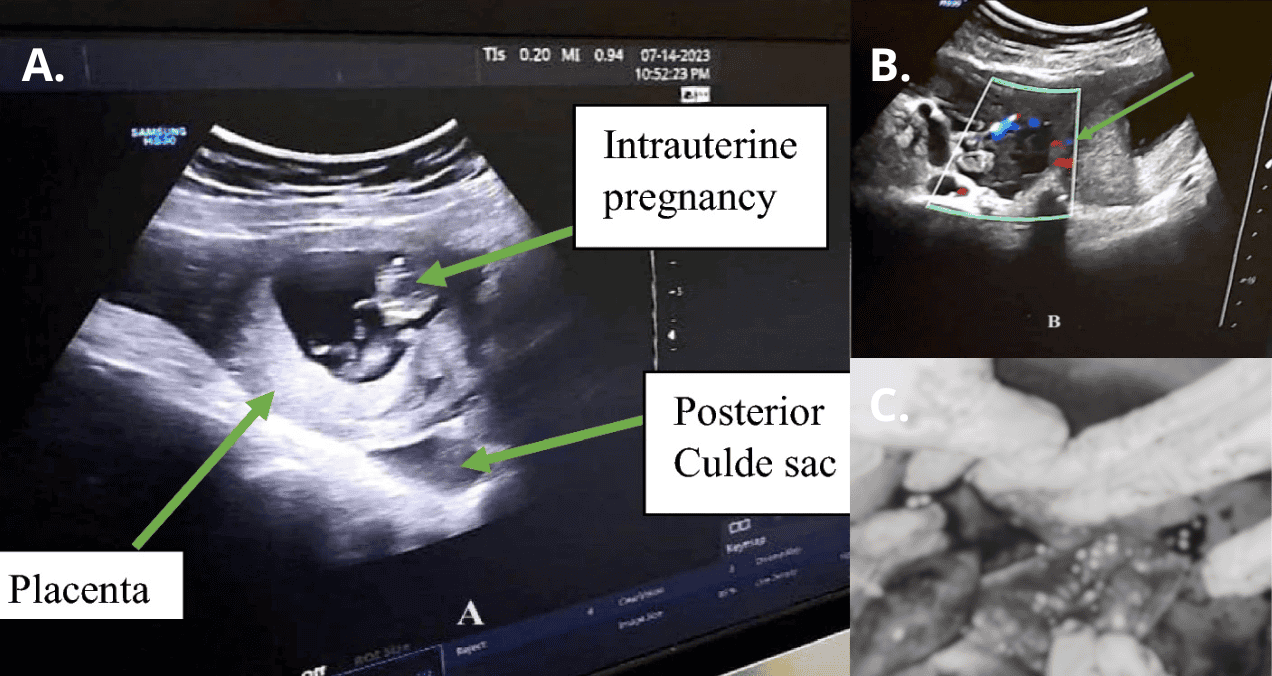

En la evaluación física presentaba signos de irritación peritoneal, taquicardia (110 lpm), presión arterial baja (100/60 mmHg) y palidez conjuntival. La ecografía inicial reveló un embarazo intrauterino viable de 10 semanas y una masa anexial derecha de 6×6 cm, con líquido libre en el fondo de saco.

Se sospechó un quiste ovárico hemorrágico roto, pero una segunda evaluación confirmó el diagnóstico de gestación heterotópica: embarazo intrauterino viable junto a un embarazo ectópico tubárico roto.

Si bien la laparoscopia diagnóstica con visualización directa sigue siendo el método de referencia, la ecografía Doppler transvaginal es la alternativa no invasiva preferida, con una sensibilidad y especificidad del 84 % y el 98 %, respectivamente.

Según la literatura médica, el uso de la ecografía transabdominal aumenta la sensibilidad para el diagnóstico de un embarazo ectópico del 53 % al 73 %. Una ecografía Doppler transabdominal mostrará un aumento del flujo sanguíneo caracterizado por un patrón de fuego de alta velocidad en la masa anexial. En este caso, el diagnóstico se realizó mediante ecografía transabdominal, que mostró un aumento del flujo sanguíneo.